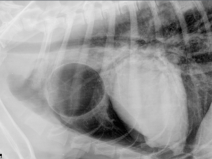

• La cardiologie du généraliste

La cardiologie est souvent considérée comme une discipline difficile et le sentiment qu’elle ne peut être envisagée qu’avec une pratique sûre de l’échocardiographie est fortement ancrée.

Or, elle est génératrice d’un grand nombre d’urgences, de suivis au long cours, de conduites thérapeutiques caractérisées par l’association de médicaments efficaces mais non dénués d’effets indésirables...

• La cardiologie du généraliste (Limoges)

La cardiologie est souvent considérée comme une discipline difficile et le sentiment qu’elle ne peut être envisagée qu’avec une pratique sûre de l’échocardiographie est fortement ancré.

Or, elle est génératrice d’un grand nombre d’urgences, de suivis au long cours, de conduites thérapeutiques caractérisées par l’association de médicaments efficaces mais non dénués d’effets indésirables....